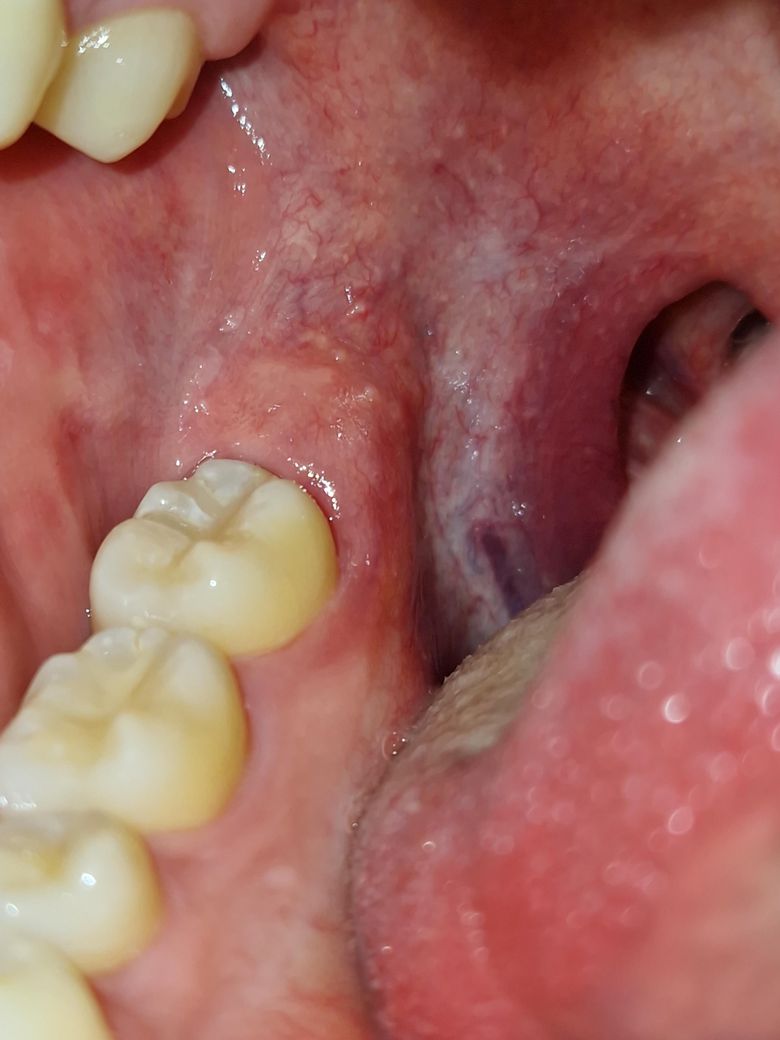

어금니 뒤 잇몸에 하얀 돌기같은게 있어요.

아프거나 불편하지는 않는데 그냥 구강 구조가 이렇게 생긴건가요?

아니면 구강 질환일까요?

일반적인 구강 구조 중 하나로 보여집니다. 정상 범주에 속하는 연조직으로 보여집니다. 하지만 해당 부분이 가렵거나 통증 및 압박감이 나타난다면 그때는 치과 방문 후 연조직에 대한 정밀 검사를 해보시는 것이 좋습니다. 그렇지 않다면 크게 걱정하지 않아도 됩니다.

잇몸 상피 조직의 이형성으로 보이는데 정확히 어떤 상태인지는 구강내과가서 조직검사를 해봐야 알 수 있습니다